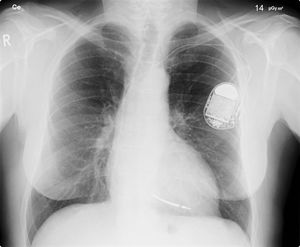

Pacemaker återkallas på grund av att de kan hackas Nästan en halv miljon pacemakers måste uppdateras Pacemaker återkallas på grund av att de kan hackas Foto: Lucier Monfilis / Wikipedia Den amerikanska myndigheten FDA (Food and Drug Administration) har beslutat att runt 465.000 pacemakers från tillverkaren Abbott måste återkallas för att installera en uppdatering rörande ett säkerhetsproblem. Det är ett antal av Abbots modeller som nu måste få sitt firmware uppdaterat men det ska vara en process som bara tar cirka 3 minuter enligt företaget. Det framgår inte exakt hur denna uppdatering går till men jag antar att det är något man måste fixa på sjukhus om man har en av de berörda modellerna. Säkerhetsuppdateringen kommer att innehålla: